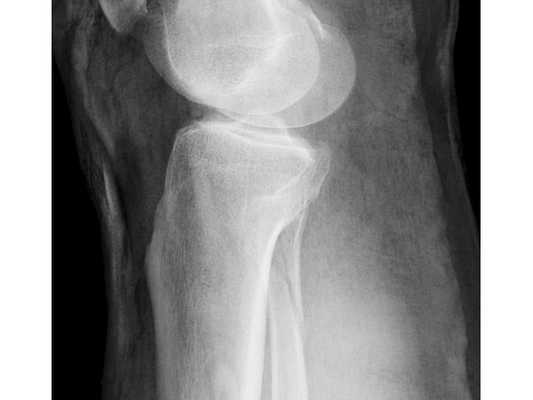

При осмотре определяется отёк мягких тканей области голеностопного сустава. Геометрия сустава изменена. Движения в голеностопном суставе ограничены болями, при пальпации пациент отмечает боли в этой области. Также при пальпации есть болезненность в верхней трети правой голени в проекции головки малоберцовой кости.

- Рентгенография правой голени на протяжении с захватом коленного и голеностопного суставов.

Закрытый оскольчатый перелом внутренней лодыжки правой голени со смещением отломков. Закрытый перелом верхней трети малоберцовой кости правой голени. Повреждение дистального межберцового синдесмоза ( соединения большеберцовой и малоберцовой костей) . Подвывих стопы кнаружи (Maisonneuve-type fracture).

2. Наличие на рентгенограммах голеностопного сустава изолированного перелома внутренней лодыжки обязывает доктора выполнить исследование голени на протяжении для выявления перелома малоберцовой кости в верхней её трети.